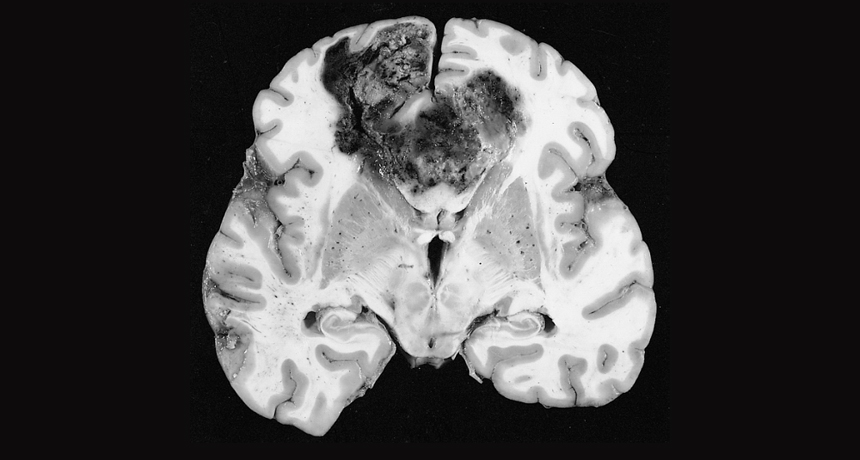

A new study suggests that certain small molecules may help kill the damaged cells that cause glioblastomas, highly malignant brain tumors.

Dr. Rodney D. McComb/Wikimedia Commons